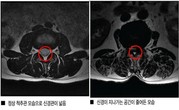

디스크·중풍 의심은 가는데 병명이…

박문수(65세)씨는 어느 날 반찬으로 올라온 멸치 볶음을 젓가락으로 집다가 손에 힘이 빠져 젓가락을 놓쳐버렸다.이후에는 다리에 둔한 감각이 느껴지기 시작했다. 박씨는 혹시 말로만 듣던 중풍이 온 것이 아닌가 걱정이 되어…

척추관협착증, 비수술 한방 ABCDE 치료효과 '굿'

어린이들의 그림동화 속에 등장하던 할머니는 언제나 지팡이를 짚고 허리가 앞으로 굽은 꼬부랑 할머니의 모습이다. 그림 속 할머니의 허리는 왜 굽었을까?오랜 기간 동안 노인과 척추질환은 불가분의 관계처럼 느껴진다. 노인…